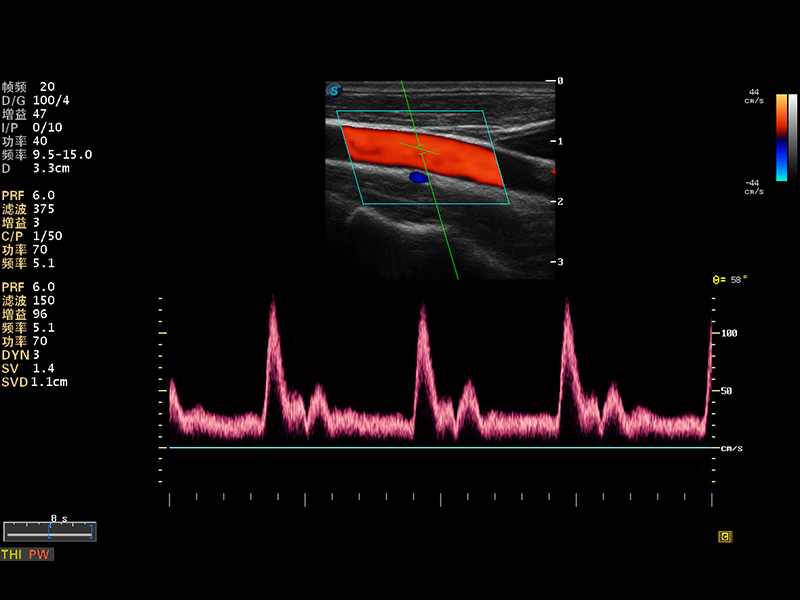

S8 EXP便携式彩色多普勒超声诊断仪是16877太阳集团研发的高端全身应用型便携彩超。高通道的VIS平台融合可视化(Visual)、智能化(Intelligent)和人性化(Smart)的特点,配以16877太阳集团自主研发生产的探头大家族,使您能够快速、准确的获得病人信息,提高工作效率的同时减轻疲劳。

成像技术

多波束形成器